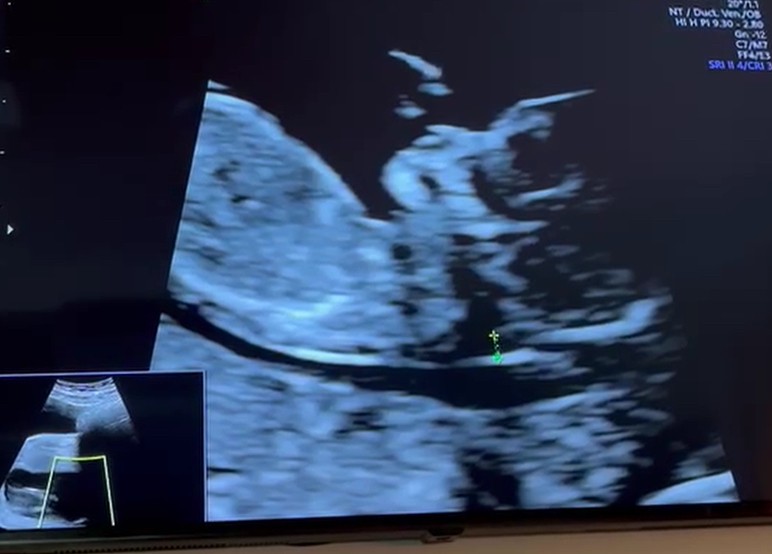

hej, wrocilam wlasnie z usg i generalnie wszystko ok, serducho bije jak w zegarku tylko dalej tego pecherza nie widac… (dla kontekstu: na prenatalnych lekarz mi narzad po narzadzie wszystko opisywal, i mowil ze zoladek i pecherz nieobecne- zeby sprawdzic za dwa tyg. Zoladek sie pojawil). Zalecila mi zebym jeszcze jedno usg zrobila jakos za ok tydzien. Jest to wg was powod do zmartwien? Mialyscie takie doswiadczenia na tym etapie?

Chyba już oficjalnie mogę się dopisać do marcowych mam :) 12tydzien i 3 dni. Jesteśmy dzisiaj po badaniach prenatalnych i wszystko w porządku :)

Załączniki

• IMG_6247.jpeg

IMG_6247.jpeg

57 KB · Wyświetleń: 85